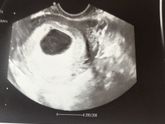

Если что у меня была анэмбриония(